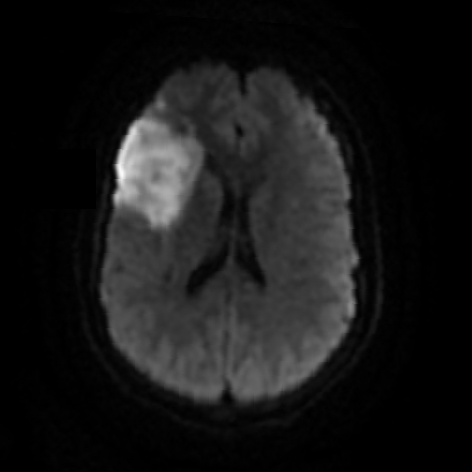

Cortical Strokes

• Most common finding (Cortically-based MCA strokes being the most common).

• Hemorrhagic conversion is common and complicates any use of anticoagulants/anti-thrombotics.